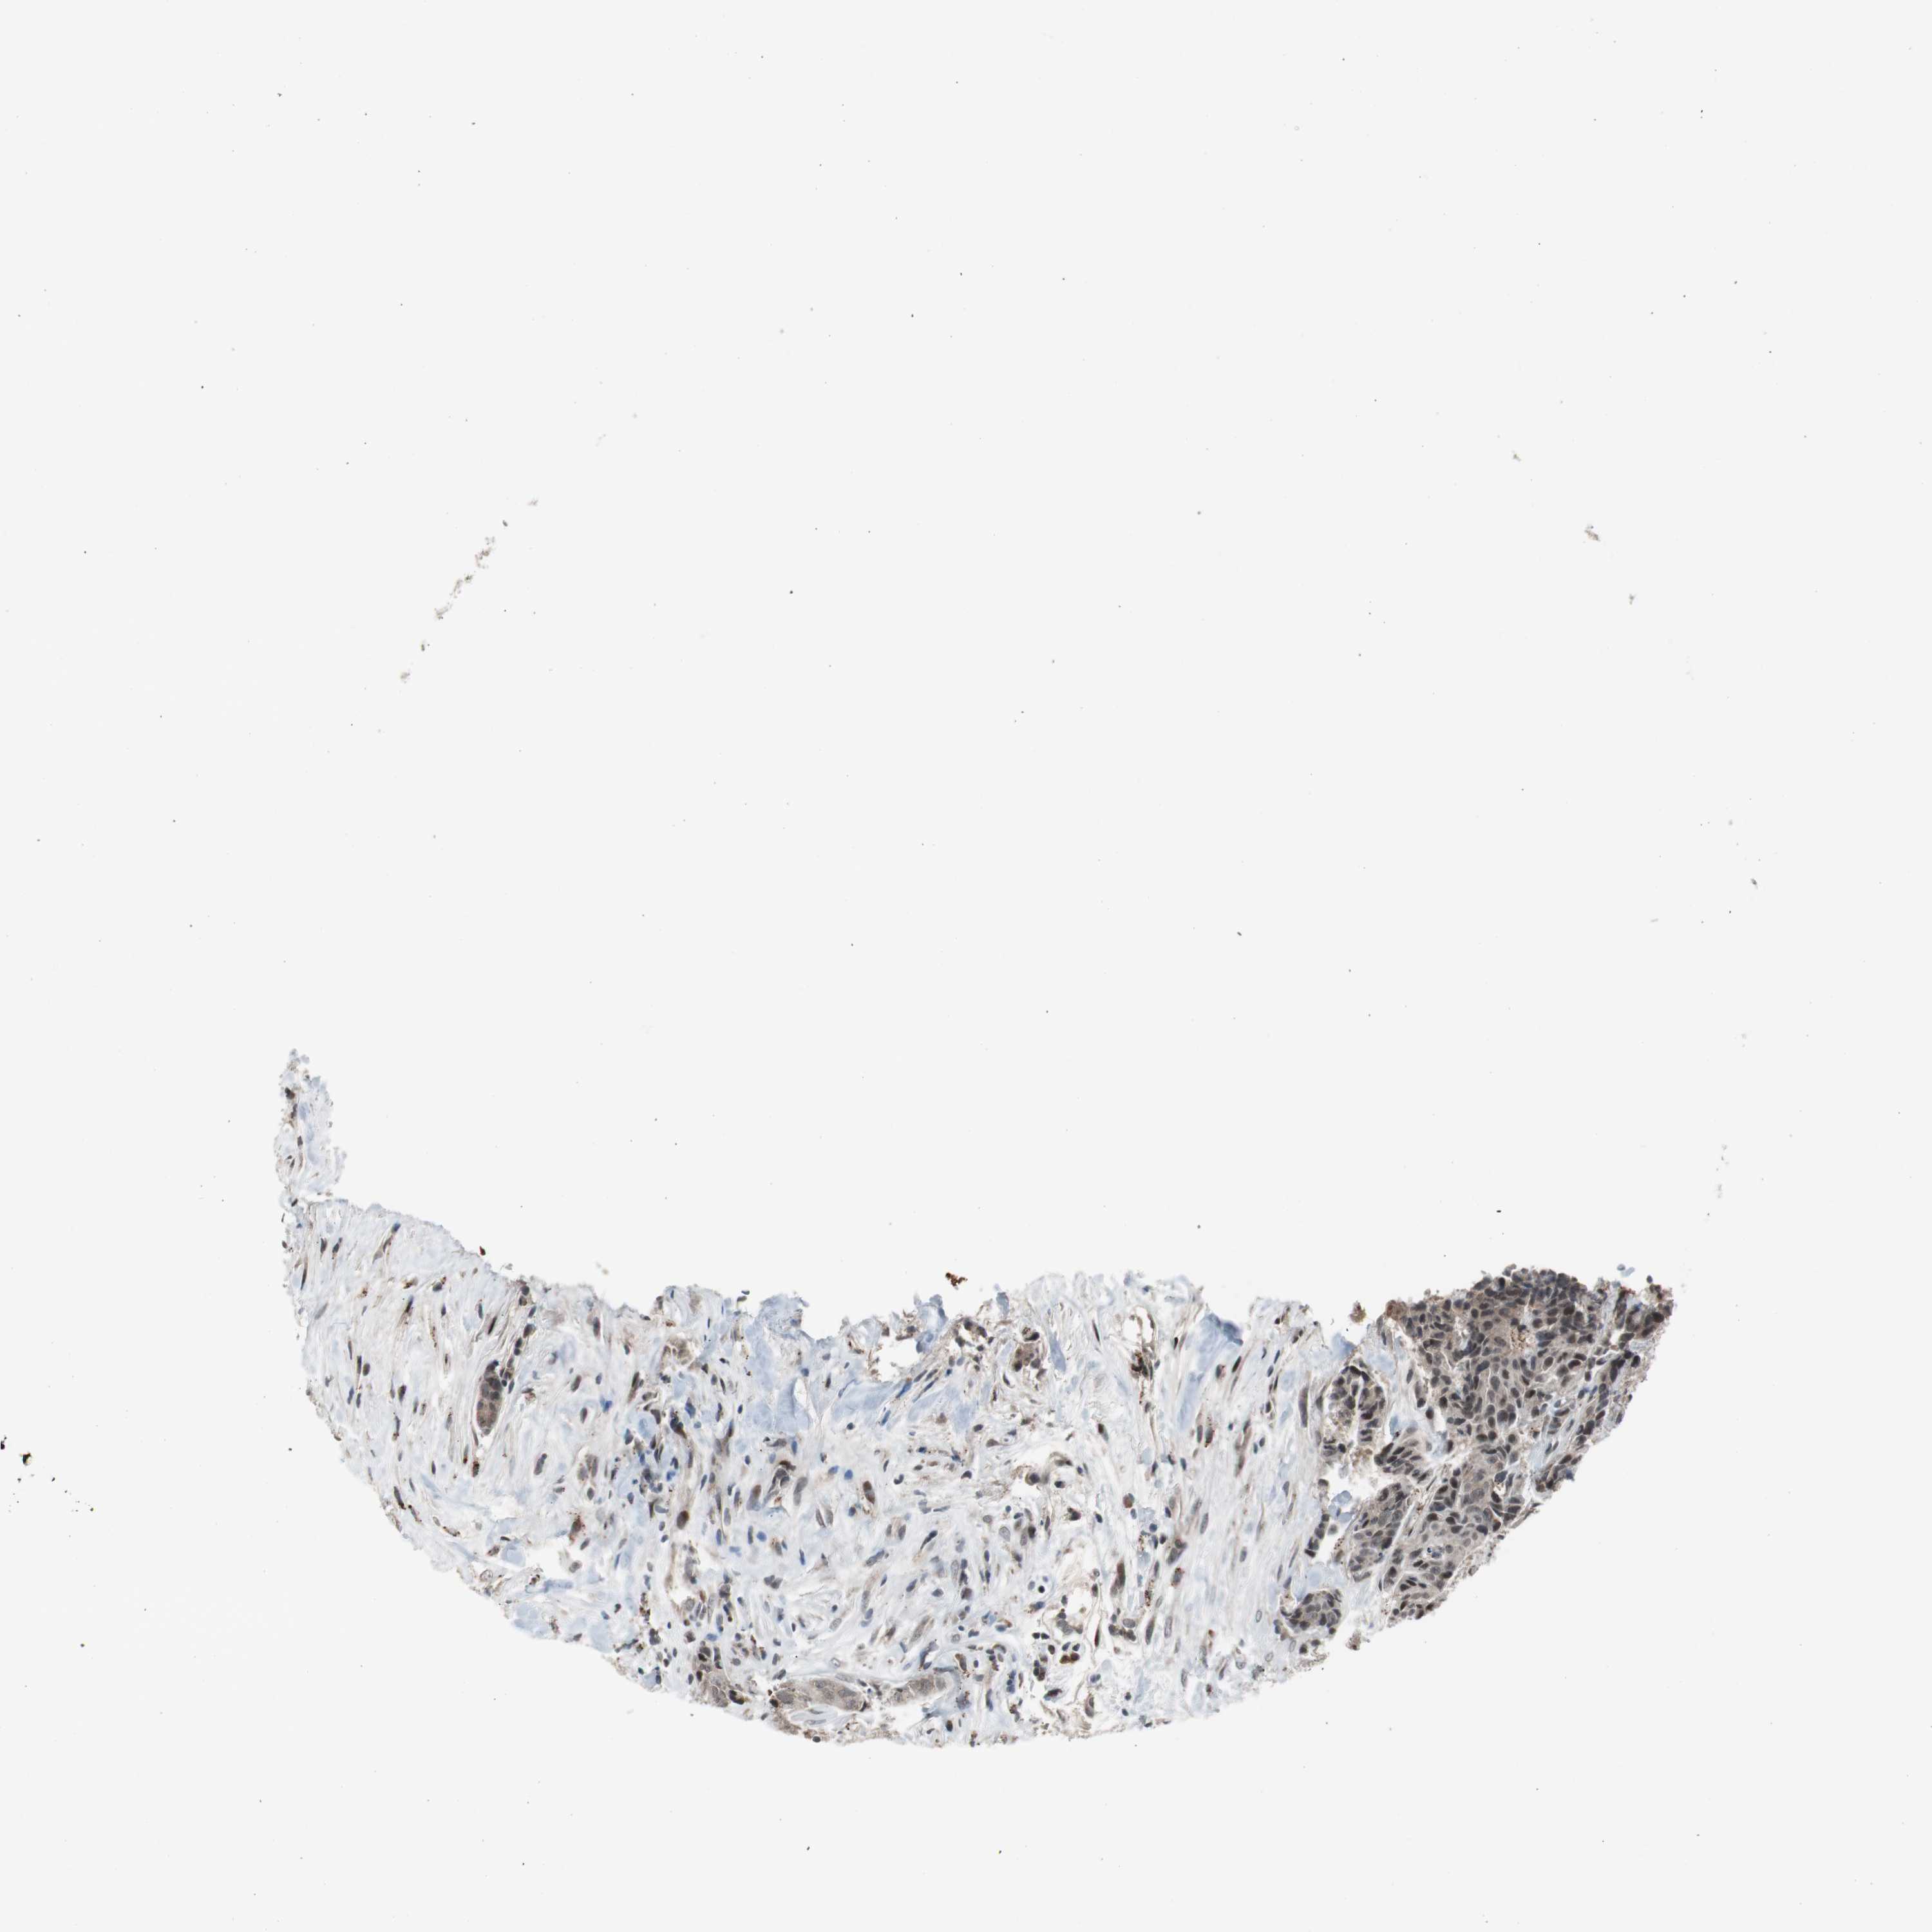

BRCA TCGA BRCA VALIDATION PROTEIN EXPRESSION